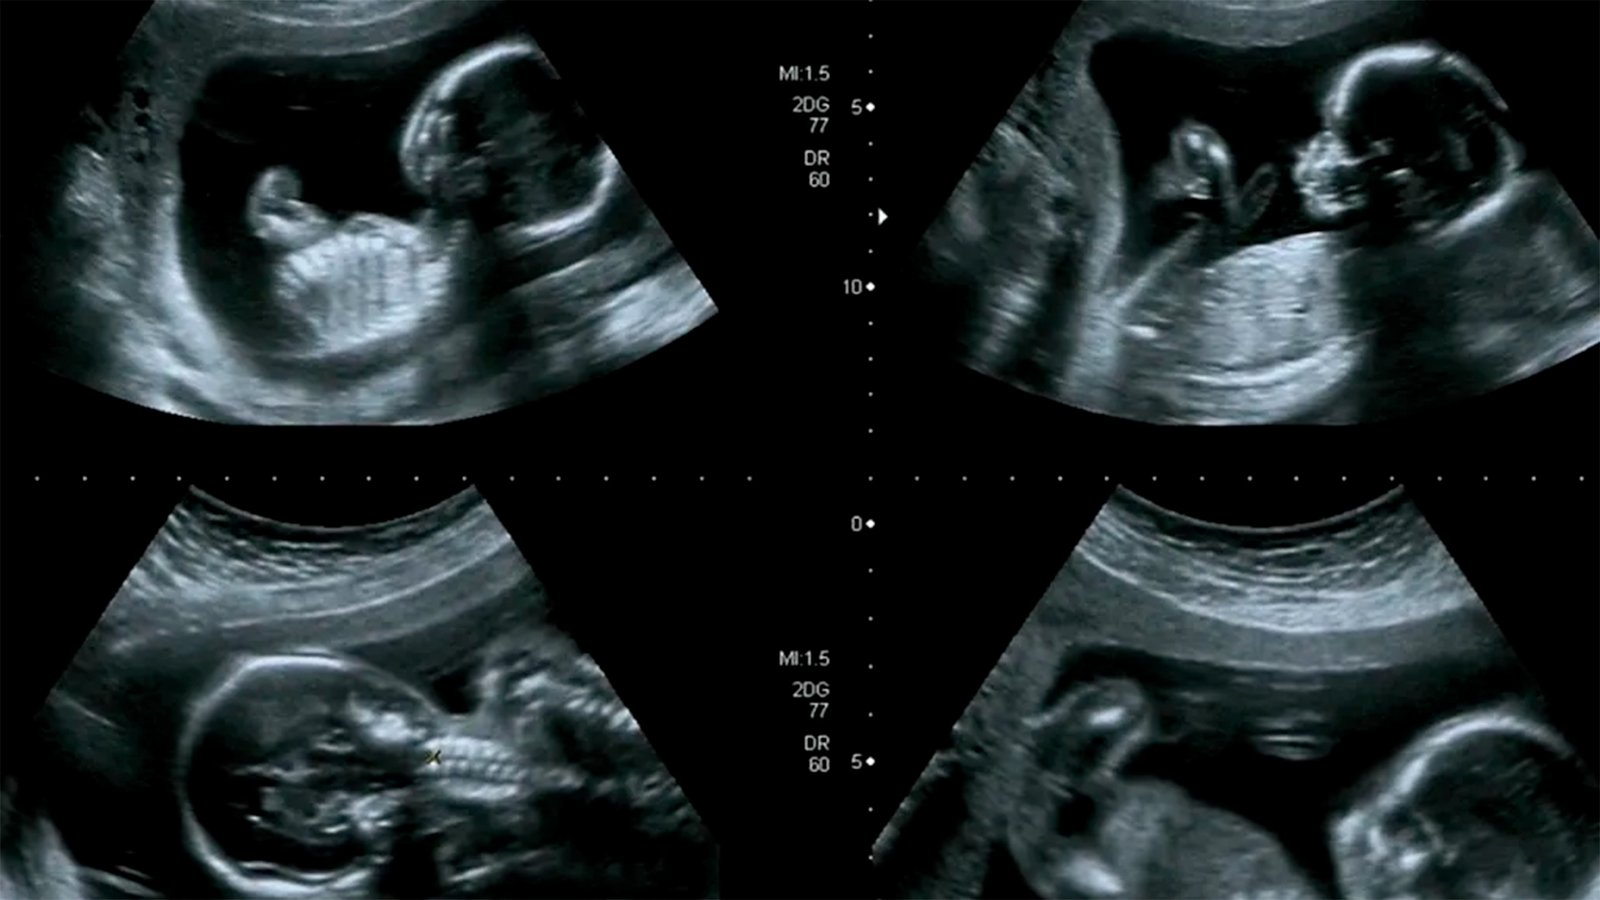

Gerar – 3º mês

Série Gerar – 3º mês